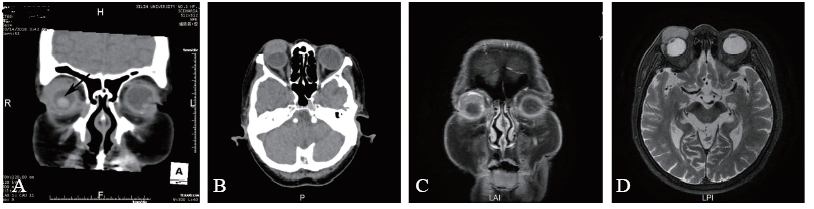

实验室检查:血常规、尿常规、空腹血糖、肝肾功能、凝血常规未见异常。眼眶CT示右侧眼睑软组织影增厚,并突入右眼眶内(图2A、B)。眼眶MRI示右侧上眼睑软组织影内见类圆形稍长T1稍长T2信号影,大小约2.7 cm×1.7 cm×1.4 cm,边界尚清(图2C、D)。

图2 一例小圆细胞恶性肿瘤患者CT、MRI检查结果

A:CT冠状位检查(病灶见黑色箭头);B:CT横断面检查;C:MRI冠状位检查;D: MRI横断面检查